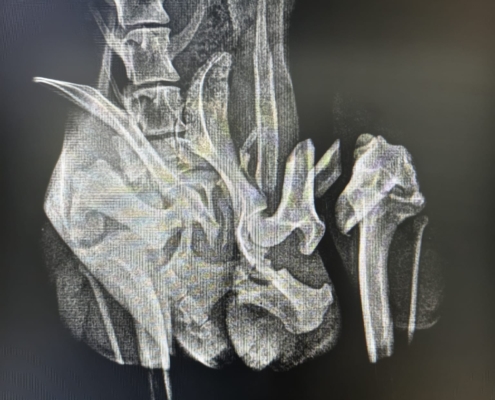

leider war sein Name durch den Umstand entstanden, dass er verletzt (vermutlich durch einen Unfall) auf der Straße gefunden wurde….

Wie lange er schon mit dieser Verletzung unterwegs war…. wir wissen es nicht… auch über sein bisheriges Leben können wir nichts sagen…

Er hat die OP gut überstanden und darf sich noch ein bisschen in der Tierarztpraxis erholen… doch dann braucht er einen sicheren Platz um wieder vollkommen zu genesen…. Leider ist es fast unmöglich vor Ort eine Pflegestelle zu finden… 🙁 und die Finderin, die sich aktuell um ihn kümmert, verlässt im März Rumänien…